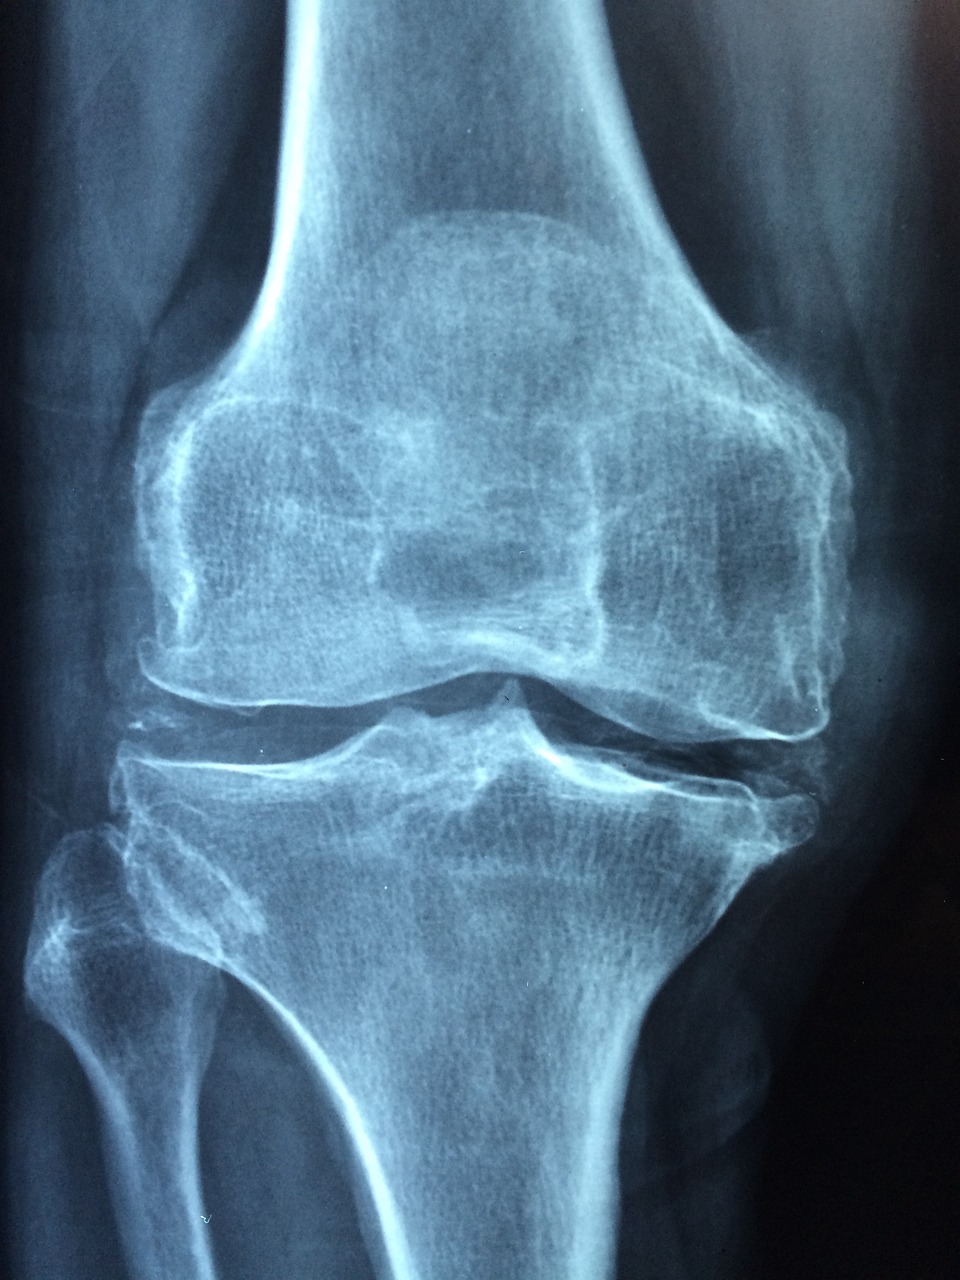

무릎 관절염이 심해지면 결국 인공관절 수술을 고민하게 됩니다.

무릎 인공관절 수술은 손상된 무릎 관절을 인공 관절로 교체해 통증을 줄이고 움직임을 되찾도록 돕는 치료 방법입니다. 기존에는 정형외과 전문의가 수술 도구를 이용해 직접 절개하고 교체하는 일반 수술 방식이 주로 사용됐습니다.

하지만 최근에는 로봇 기술을 활용한 수술 방식이 새롭게 주목받고 있는데요. 3D 영상으로 무릎 상태를 정밀하게 분석한 뒤, 로봇 팔이 수술 부위를 정확하게 절삭하고 인공관절을 삽입합니다.

정확도가 높기 때문에 출혈이 적고, 수술 후 통증도 줄어드는 편이며 회복 속도 역시 빠른 것이 특징입니다. 다만 로봇 장비를 사용하는 만큼 수술 시간은 일반 수술보다 조금 더 소요될 수 있고 전체 비용에서도 차이가 발생할 수 있습니다.